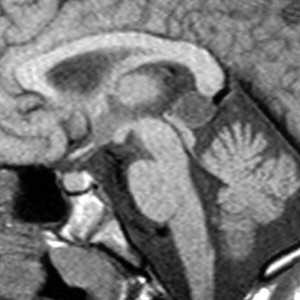

Коллоидная киста - это врождённое нейроэпителиальное образование. Коллоидная киста выстлана эпителием и имеет фиброзную капсулу. Она составляют около 1-2% объемных внутричерепных образований. Обычно диагностируются в возрасте между 30 и 50 годами. Всегда расположена в переднее-верхнем отрезке III желудочка между отверстиями Монро. Контур ее четкий, форма округлая, содержимое бывает неоднородное. Размер от 3 мм до 4 см, при больших размерах она закрывает отверстия Монро и вызывает окклюзионную гидроцефалию. Сигнал зависти от примеси белка к ликвору. При наличии белкового мукоидного содержимого киста гиперинтенсивна на Т1-взвешенных МРТ головного мозга и гипоинтенсивна на Т2-взвешенных МРТ, но встречаются варианты гиперинтенсивные на МРТ головного мозга обоих типов взвешенности кольцевидные или смешанные. При МРТ головного мозга с контрастированием усиления сигнала не наблюдается.

Киста кармана Ратке представляет собой редко встречающееся образование из остатков эмбриональной эктодермы (щель Ратке), расположенное между долями гипофиза. Выявляется в любом возрасте, но чаще в 50-60 лет. Клинические проявления связаны с масс-эффектом. При МРТ головного мозга выявляется небольшая (3-5мм) киста с четким контуром, без отека вокруг, однородная по структуре. Сигнал на МРТ головного мозга зависит от содержимого. При серозном содержимом сигнал типично жидкостный, при мукоидном киста светлая на Т1-взвешенных МРТ головного мозга. В 70-80% случаев внутри кисты выявляется неконирастирующийся узелок («пятно») - признак патогномоничный для кисты кармана Ратке. В редких случаях киста достигает больших размеров и даже выходит за пределы седла. Стенка кисты иногда усиливается при МРТ головного мозга с контрастированием. Дифференциальная диагностика при МРТ головного мозга должна проводиться с арахноидадьной и эпидермоидной кистами, тератомой, кистозной аденомой гипофиза и краниофарингиомой. Иногда при МРТ головного мозга киста кармана Ратке напоминает “пустое” турецкое седло. При маленьких размерах кисты ее на до дифференцировать на МРТ с микроаденомой гипофиза.